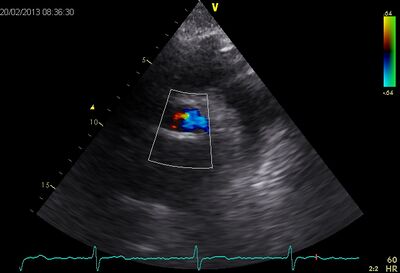

| Suprasternal apd (color doppler) | Dilated apd (Plax PV) |